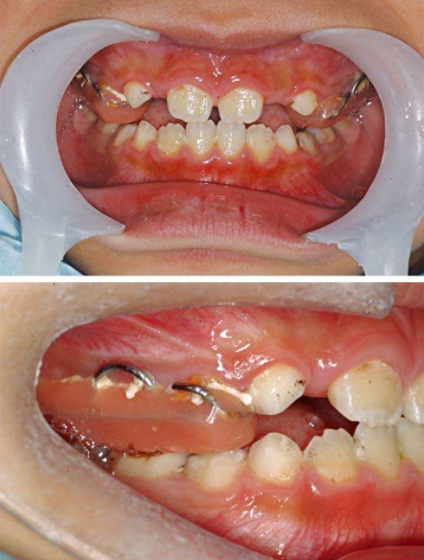

4 个别前牙反𬌗

原则是如果有咬𬌗创伤,要做。如果暂时没有咬𬌗创伤,可以再等等。

如何鉴别咬𬌗创伤?

看看下前牙有没有牙龈退缩。有牙龈退缩说明有咬𬌗创伤,这就得做。使用𬌗垫双曲舌簧活动矫治器,或者有时候上颌2-2粘托槽,镍钛丝排齐也能解决这个问题。